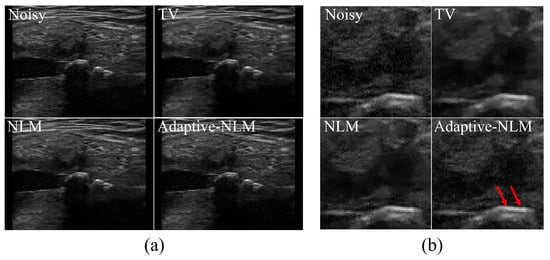

3. Results and Discussion